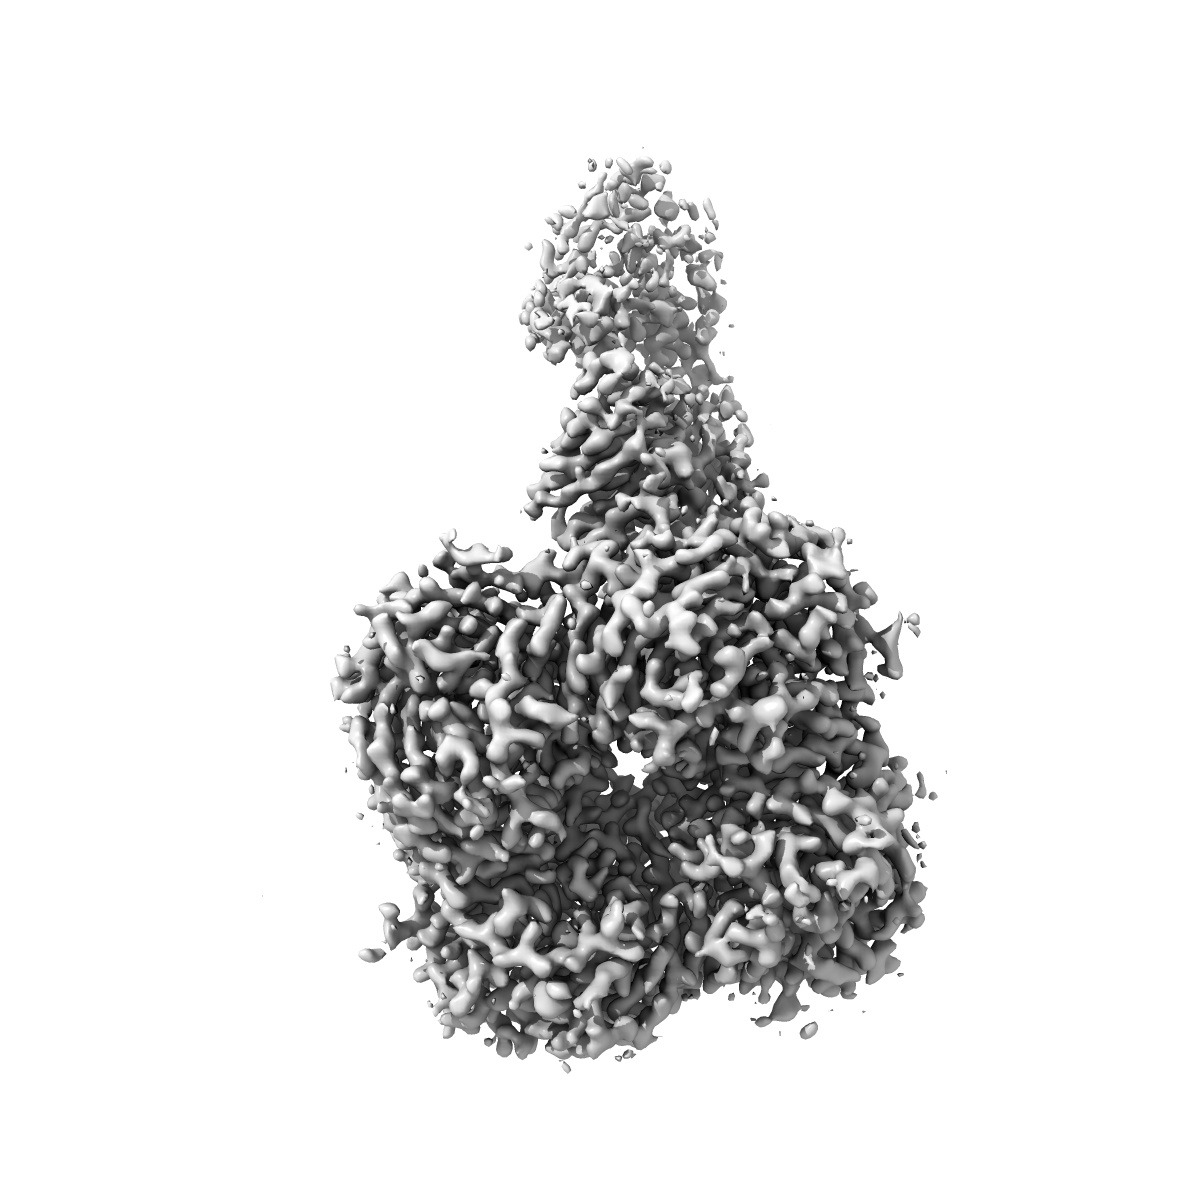

Cryo-EM structure of FNI9 IgG in complex with influenza virus neuraminidase from A/Kansas/14/2017 (H3N2)

Single-particle2.97 Å

Sample: FNI9 IgG in complex with influenza virus neuraminidase from A/Kansas/14/2017 (H3N2)

Structural basis of broad protection against influenza virus by human antibodies targeting the neuraminidase active site via a recurring motif in CDR H3.

(2025) Nat Commun , 16 , 7067 - 7067